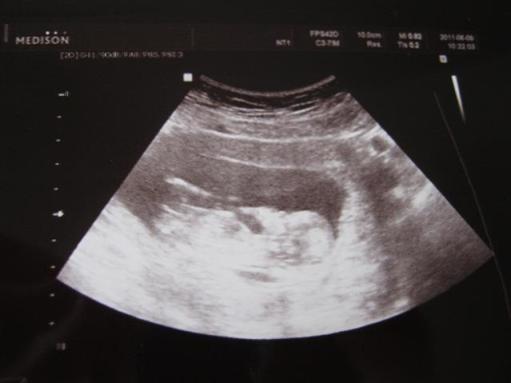

Eddig minden rendben volt, illetve a 12 hetes genetikai UH-n volt egy kis riadalom, a fiatal orvos nem találta az orrcsontot, vagyis nem tudta eldönteni, hogy azt látja-e vagy valami szövetet??? Ekkor egy genetikus is megnézte Bogyókát (Dr. Bárdos), és mindent rendben talált. Egy plusz vizsgálatot is végzett: ductus venosus flow, ez is rendben volt.

Fentiekből okulva a 18. héten az Istenhegyi útra megyek genetikai UH-ra, nem szeretnék még egyszer hasonló rossz élményt.